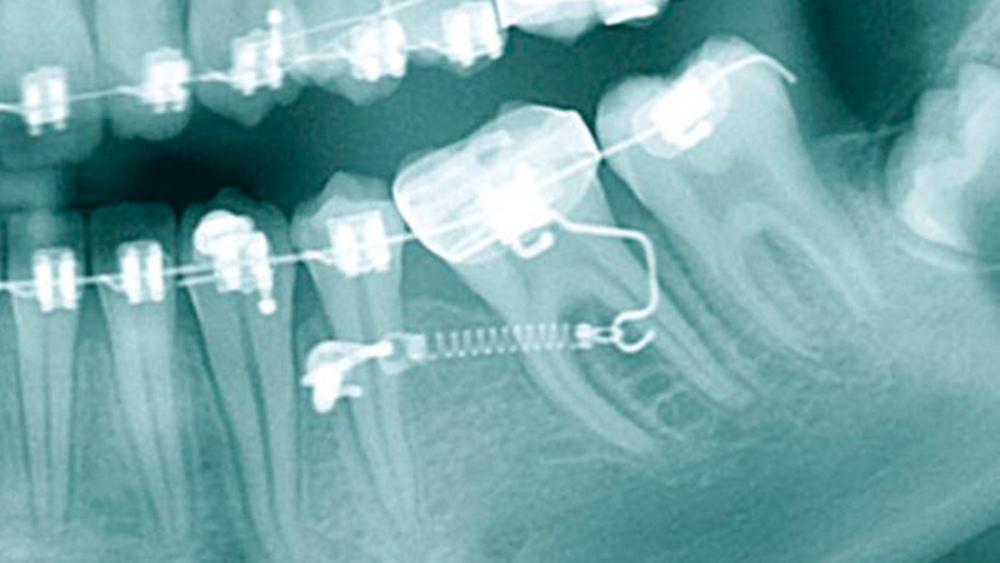

Seit Einführung der skelettalen Verankerung ist der orthodontische Lückenschluss ohne unerwünschte kollaterale Zahnbewegungen wie beispielsweise Mittellinienverschiebungen möglich. Das macht ihn zu einer attraktiven therapeutischen Alternative. Der Beitrag skizziert Indikationen und Abwägungen für den Lückenschluss beim Kieferorthopäden.

Mit den in den letzten Jahren ausgeweiteten Indikationen ist auch die Notwendigkeit verbunden, mehr Risikofaktoren zu kontrollieren. Der Beitrag erörtert verschiedene Indikationen und gibt einen praxisnahen Einblick in die implantologische Lückenversorgung.

Die bislang selten angewandte Zahnextrusion bietet die Chance, selbst Zähne mit tiefen Defekten erfolgreich zu behandeln. Die kieferorthopädische Extrusion hat zudem den Vorteil, dass im Fall des Zahnverlusts eine „augmentierte“ Einzelzahnlücke verbleibt, die eine weitere implantologische Versorgung erleichtern kann.